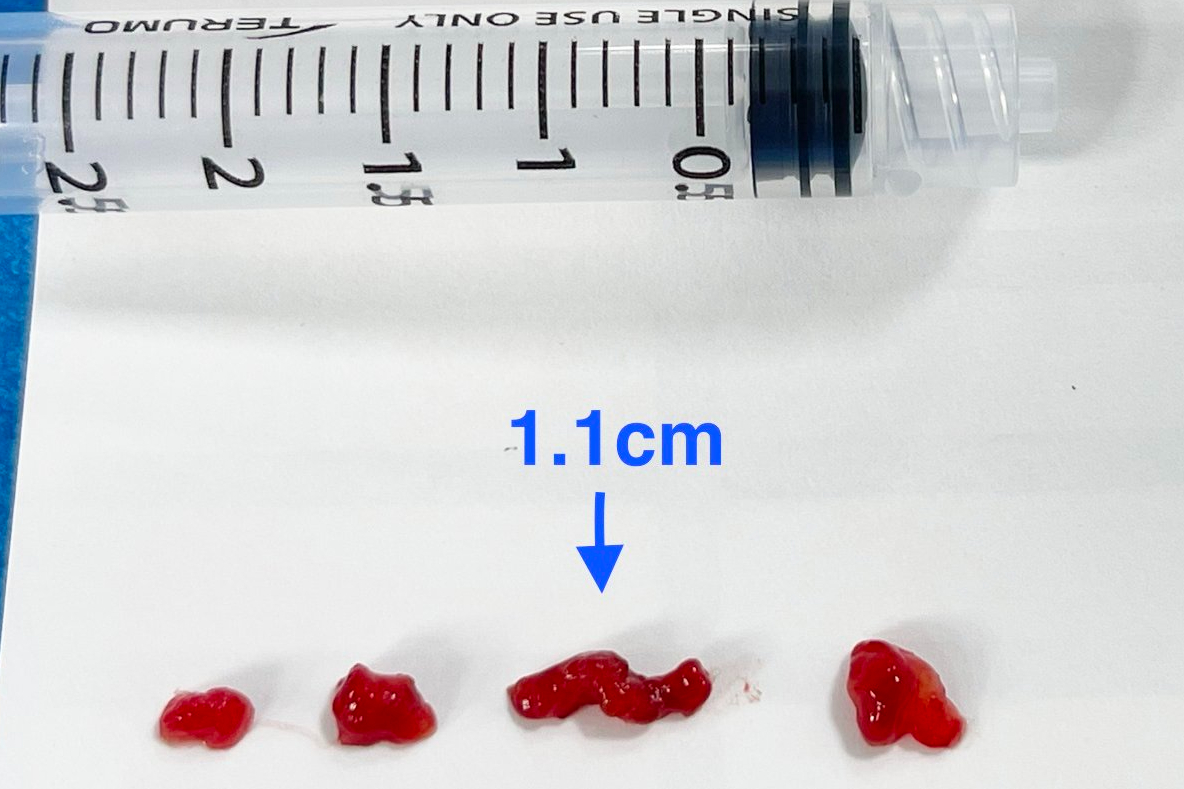

聯新國際醫院表示,該名學生被送往該院急診,影像檢查結果出爐後,神經內科醫師李振華迅速判讀,確定為左側中大腦動脈栓塞造成缺血性腦中風。在與家屬充分溝通後,影像醫學科主任暨取栓醫師郭葉璘隨即與取栓團隊進行急性腦中風顱內動脈血栓移除(Intra-arterial thrombectomy, IAT),並從腹股溝導引導管至左側中大腦動脈阻塞處,採用強力抽吸方式清除血栓。手術從開始到打通血管僅約10分鐘,成功取出4個血栓,最大達1.1公分。術後患者血流恢復暢通。